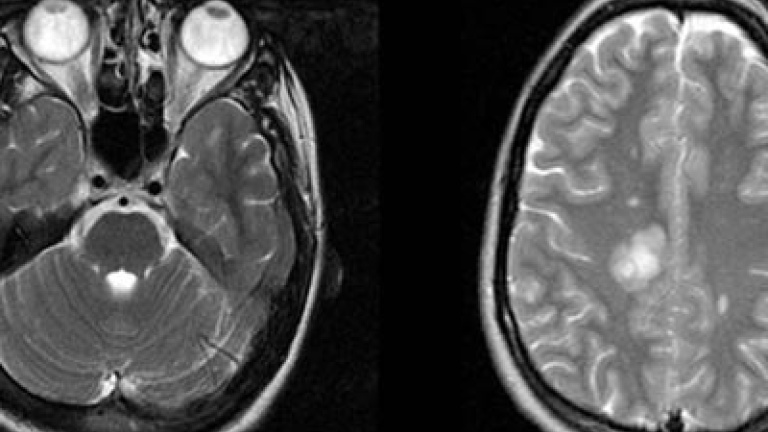

Neurocientíficos de la Universidad de Berkeley (EEUU) han localizado las zonas del cerebro donde se llevan a cabo los cálculos que pueden conllevar un comportamiento adictivo y compulsivo. Según publican hoy en Nature Neuroscience, la actividad de las neuronas situadas en las corteza orbitofrontal y la corteza cingular anterior del cerebro es la que regula estas decisiones.

Lo que observaron es que en la corteza orbitofrontal se regulaban la actividad neuronal según el valor de una decisión; por ejemplo, el comportamiento de las neuronas cambiaba según se tomaba una decisión con implicaciones u otra sin importancia. En los monos con esta zona dañada, la importancia de la decisión no influía en la actividad neuronal. En la corteza cingular, lo que regula es la memoria sobre las malas decisiones, lo que hace que alguien con daños en la zona cometa el mismo error una y otra vez.